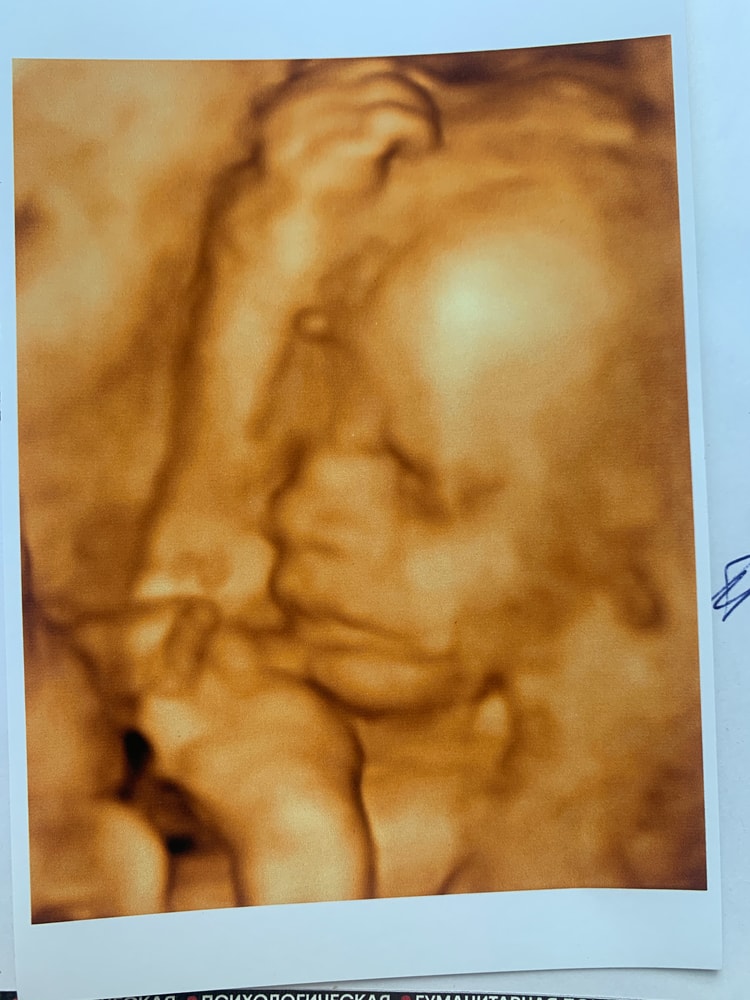

25,3 3д узи)

Еще не родился, уже чем-то недоволен 😂

мой сыночек 🥰

Сын весит 880 грамм, у меня прибавка 6 кг, очень надеюсь что это просто отек из-за того, что на улице вторую неделю +30

такой уже человек, я не могу 🥹🥹